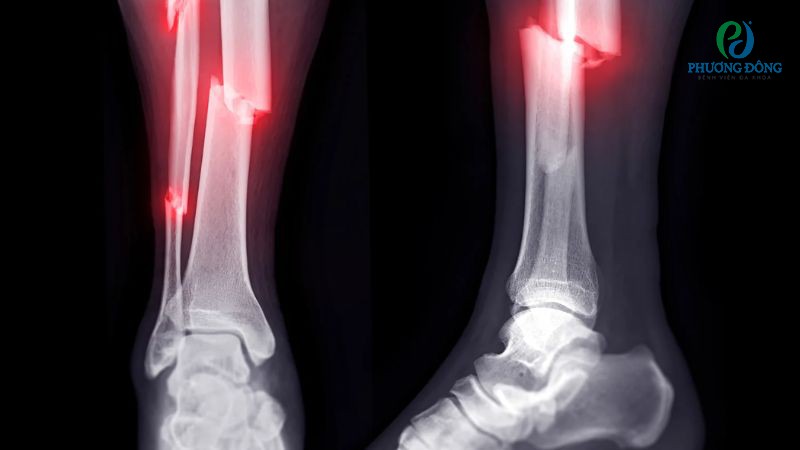

Hình ảnh trên phim X-quang

Xương gãy cần được chẩn đoán với xét nghiệm hình ảnh học, X-quang là phương tiện phổ biến nhất. Nếu phim X-quang chụp sau vài tuần hoặc vài tháng gãy, khe nứt giữa hai đầu xương không xuất hiện cầu xương, mô xương mới chậm phát triển thì có thể khả năng quá trình hồi phục không đạt hiệu quả.